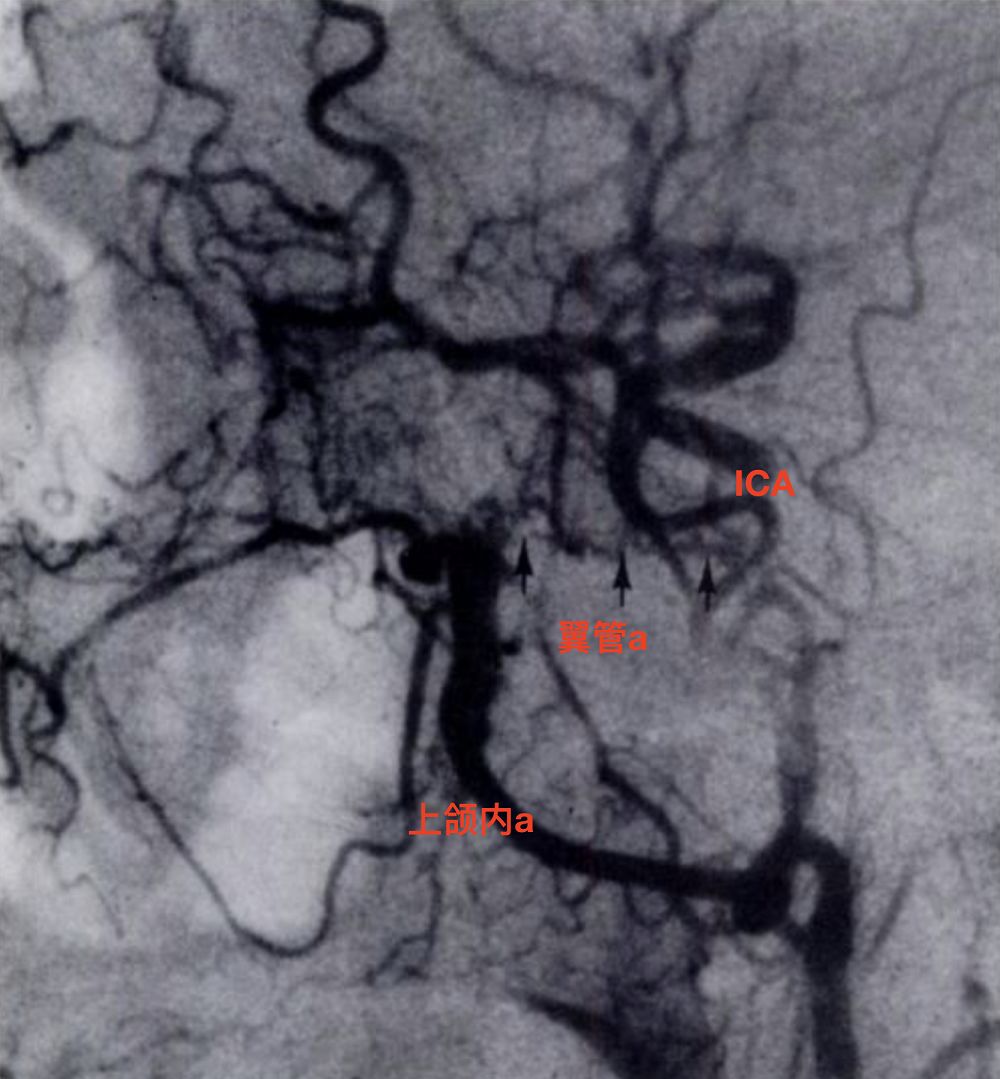

颈内动脉侧位(左)和正位(右)显示翼管动脉(小箭)发自颈内动脉岩段,向前通过翼管,与上颌内动脉远端(大箭)吻合(Osborn, 1980)。